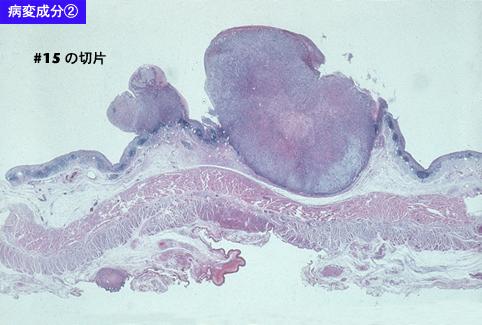

部位(按器官分)食道/2个以上

检查方法病理切片(微观)

肿瘤的肉眼分类0型(表在型)/其他

肿瘤最大直径40以上

肿瘤的深度sm